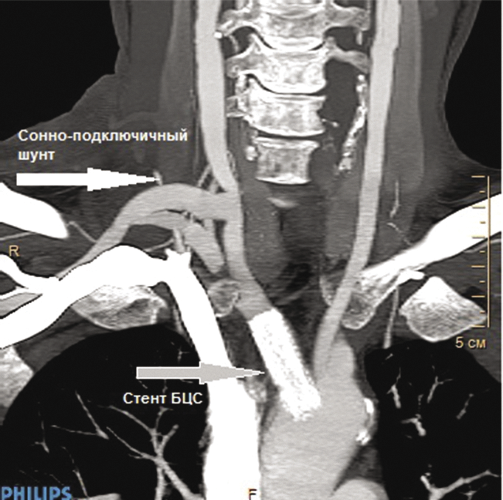

При физикальном осмотре в послеоперационном периоде имеются отчетливая пульсация правой ОСА и артерий правой верхней конечности на всех уровнях, умеренный систолический шум в проекции шунта. На КГ с контрастным усилением через 7 дней и через 6 месяцев после операции визуализируется нормальная проходимость имплантированного стента БЦС и сонно-подключичного шунта (рис 4, 5). Пациент выписан с рекомендацией двойной антитромбоцитарной терапии (аспирин 75 мг/сут и клопидогрель 75 мг/сут), антигипертензивная терапия (престариум 2,5 мг/сут и бисопролол 2,5 мг/сут) и терапия, направленная на снижение уровня холестерина (розувастатин 10 мг/сут).

Рис. 4. КТ с контрастным усилением через 6 месяцев после операции: 3D–реконструкция, нормальная проходимость сонно-подключичного шунта и имплантированного стента брахиоцефального ствола

Рис. 5. КТ с контрастным усилением через 6 месяцев после операции: нормальная проходимость сонно-подключичного шунта и имплантированного стента брахиоцефального ствола